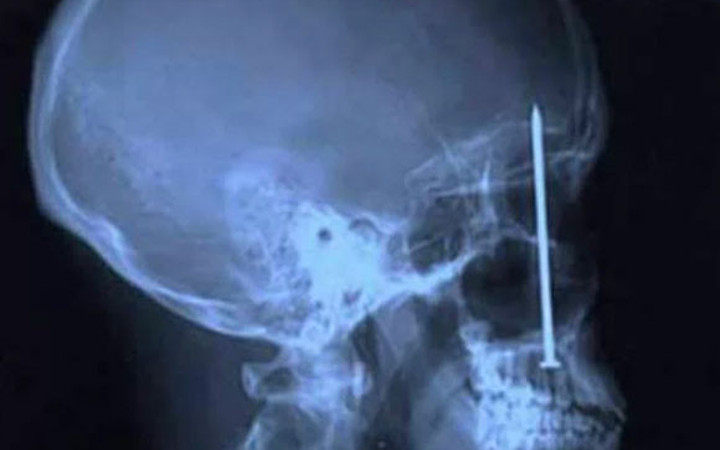

Diş ağrısından fazlasıbu xray'in sahibinin o çiviyi oraya sokmasından daha ilginci, diş ağrısı sebebiyle dişçiye gittikten sonra orada bir çivinin olduğunu farketmesi..

Diş Ağrısından Fazlası

Bu Xray'in sahibinin o çiviyi oraya sokmasından daha ilginci, diş ağrısı sebebiyle dişçiye gittikten sonra orada bir çivinin olduğunu farketmesi..